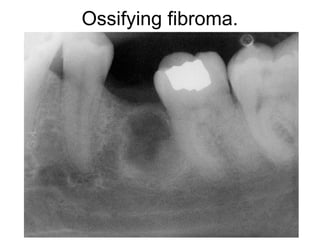

Ossifying fibroma.

Ossify ing fib roma. This low-magnification photomicrograph showsa well-

circumscribed solid tumor mass.Trabeculae of bone and droplets of cement um-like

material can beseen forming within a background of cellular fibrous connective

tissue.